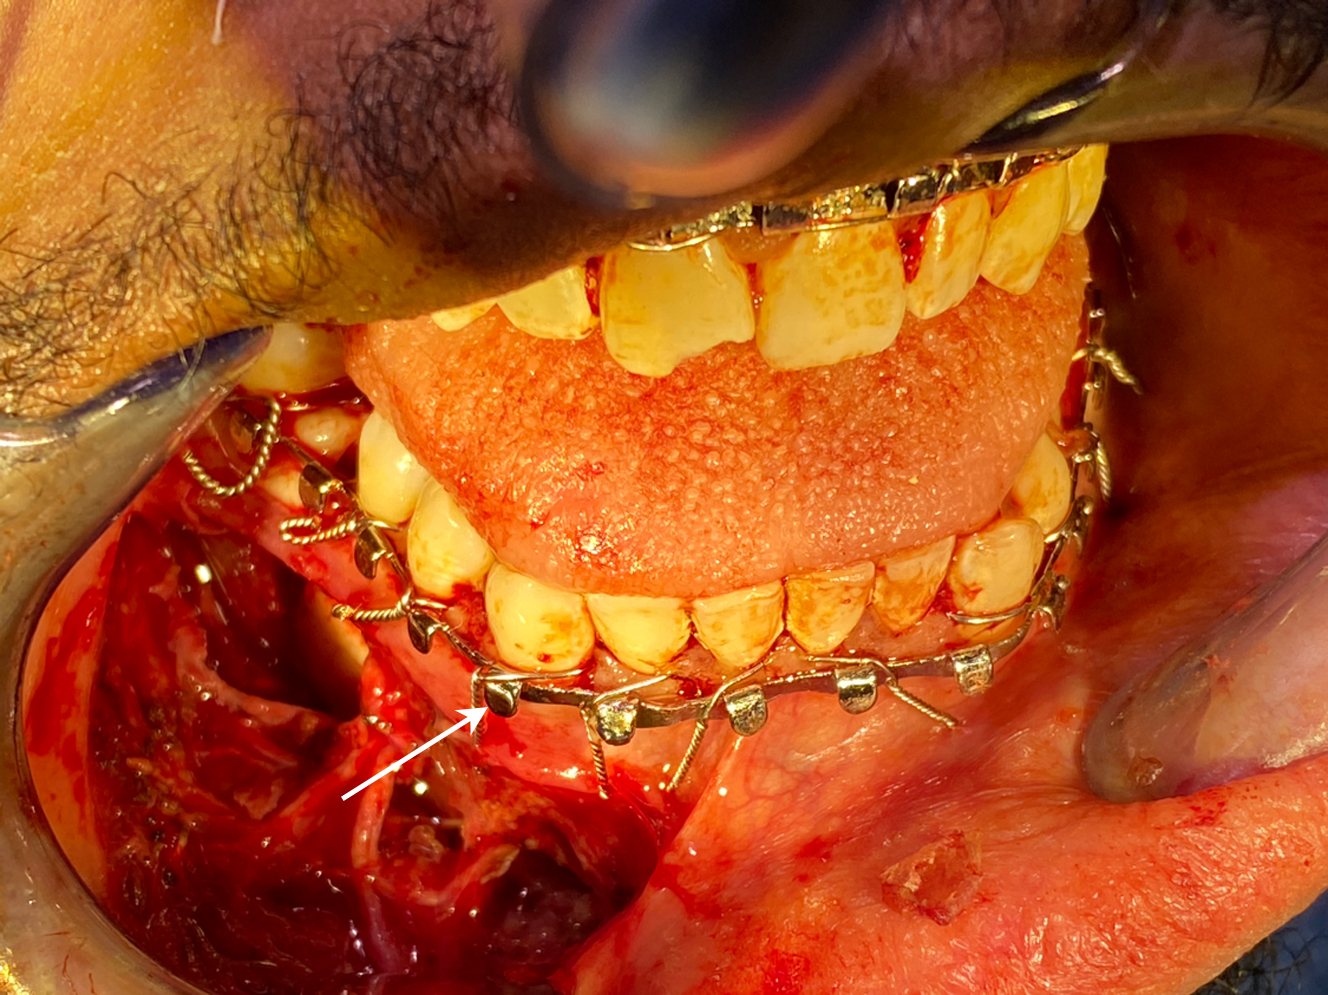

Physical examination often begins with an evaluation of external and internal lacerations. Mandible body fractures involving teeth or gingiva are technically open mandible fractures. Completing a comprehensive head and neck examination helps identify additional craniofacial injuries. A complete cranial nerve examination should be performed with particular focus on lower lip and chin sensation. Gentle palpation of the mandible may identify areas of tenderness, step-offs, and bony mobility, indicating fracture instability. Maximal interincisal distance should be evaluated to assess for trismus. Normal interincisal distance varies depending on age, body habitus, and sex and is a minimum of 30 to 40 mm. In the setting of mandible fracture, trismus is typically secondary to muscle spasm and pain and resolves with anesthetic agents. In rare cases, a bony restriction may result in a physical block limiting transoral airway management. Bilateral mandibular body fractures can cause airway obstruction if an unstable central mandible fragment produces posterior tongue prolapse. Emergent intervention may include anterior traction on the tongue to support the airway before definitive airway management.

The gold standard for identification and evaluation of mandible fractures is a maxillofacial computed tomography (CT) with cuts at 1 mm or less. Three-dimensional reconstruction of CT scans facilitates understanding of geometric relationships and fracture fragment orientation. However, minimally displaced or hairline fractures may be missed due to volume averaging. The axial, coronal, and sagittal cuts should be carefully evaluated for every patient. Panoramic tomography (eg, panorex) may be used for evaluation of mandible fractures and involves lower cost and radiation exposure. Some surgeons may routinely use this modality of imaging, particularly for postoperative assessment of plating ( Fig. 5 ). However, the lack of 3-dimensional relationships makes appreciation of fracture angulation difficult. CT has higher sensitivity in fracture identification and decreased interpretation error.